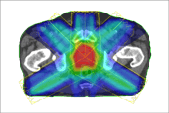

Axellis Crystalline Tungsten IMRT Compensators reduce peripheral radiation exposure and establish a new standard

in safety and accuracy due to their design, improved attenuation and reduced peripheral radiation leakage. Axellis

Individually prepared compensators enable delivery of a precise radiation dose to the tumor site, especially for treatments

requiring high resolution such as paediatrics and where tumors lie close to other critical organs such as head and neck, spinal, breast, prostate or lung.

Tungsten IMRT delivers a prescribed, homogeneous radiation dose to tumors while minimising collateral damage to surrounding

organs and tissues. Due to their highly accurate attenuation Axellis compensators can be particularly beneficial in treating paediatric patients,

head and neck, prostate, lung and breast tumors where proximity to other critical organs may be challenging.